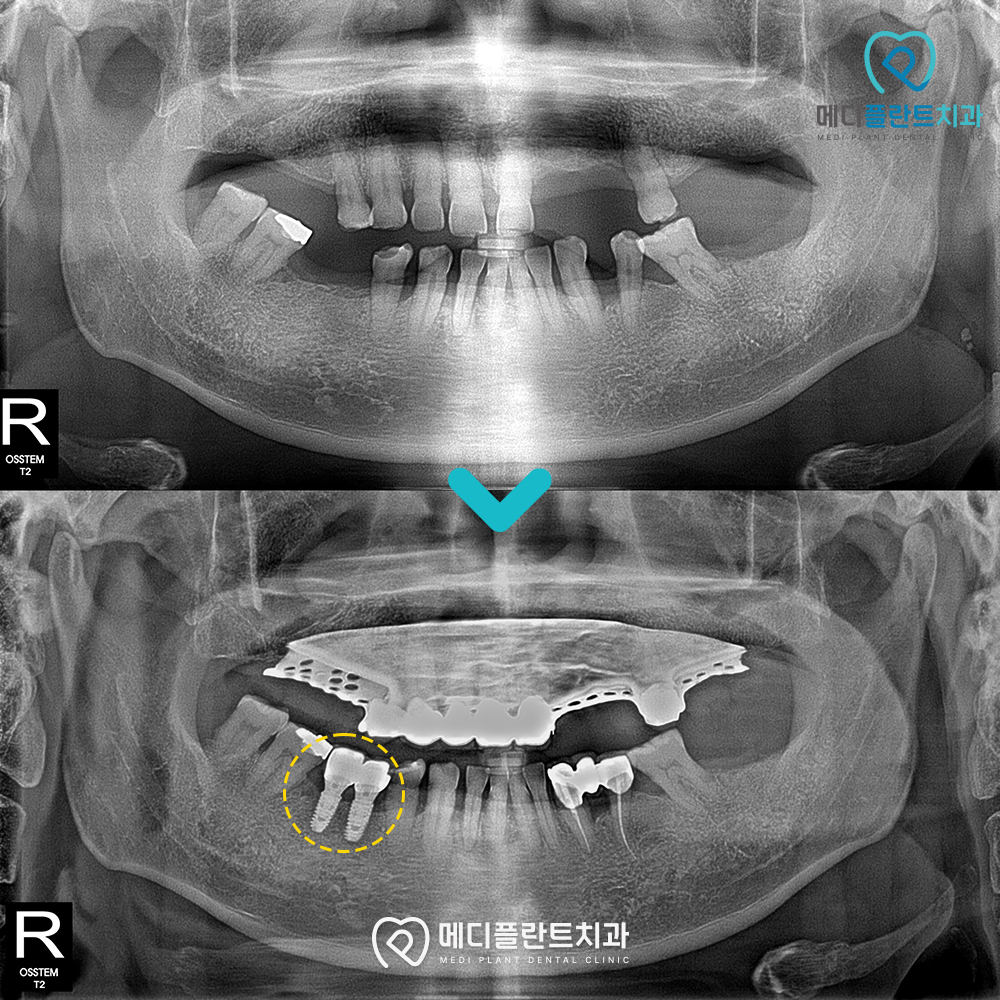

치료받으신 환자분의 사진을 소개해드리겠습니다.

이 환자분은 치아가 많이 상실되고

상태가 좋지 않아 틀니 치료와 임플란트를 진행하셨습니다.